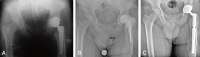

Materials and methods: A retrospective review of 64 consecutive patients was conducted: 34 underwent two-stage revision using a cement spacer (group A), 30 underwent two-stage revision without a spacer (group B). At the final follow-up, functional evaluation of patients with a THA in site, without PJI recurrence, was performed using the Harris hip score (HHS). Measurement of limb-length and off-set discrepancies was performed using anteroposterior pelvic X-rays.

Results: Most patients in group B were older with more comorbidities preoperatively. Thirty-three patients (97.1%) in group A underwent THA reimplantation versus 22 patients (73.3%) in group B (P<0.001). No significant differences in limb-length and off-set were observed. The results of functional evaluation performed during the final follow-up (mean, 41 months) showed better function in patients in group A (mean HHS, 76.3 vs. 55.9; P<0.001).